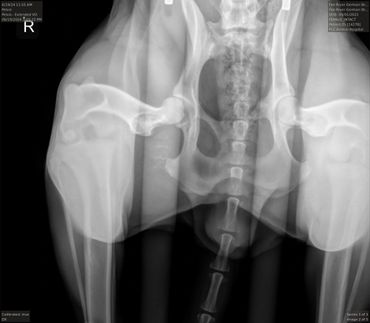

Hips (SV): Normal

PennHIP: L: 0.19. R: 0.33.

Elbows (SV): Normal

LUW (SV): 0